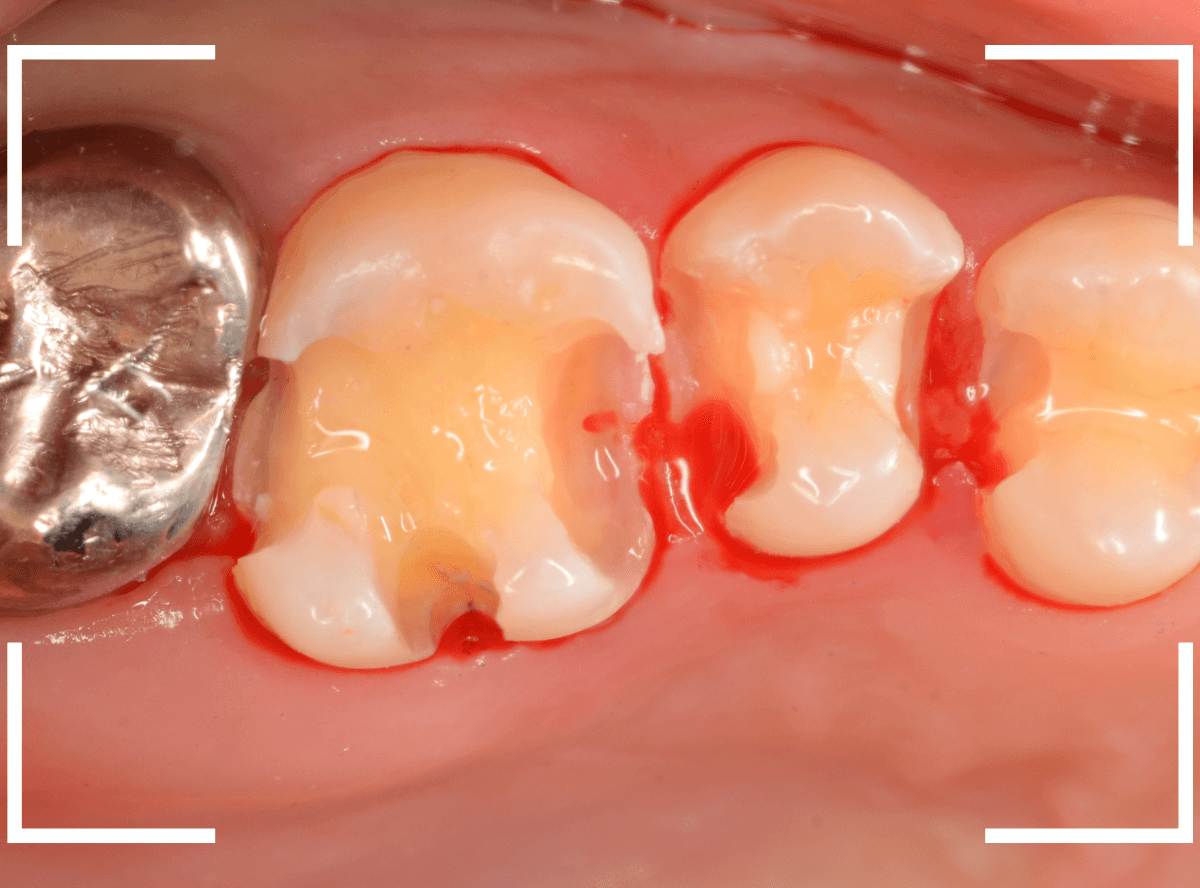

「つめものが外れて、噛むと痛い」という訴えで来院された患者さんさんです。

一見で、表面が虫歯になっているのと、レジンが劣化しているのがわかります。

レントゲン写真で確認します。

〇部が当該の歯です。

症状もあるので、虫歯が深そうですが、全体がもやっとして、どこからどこまで虫歯なのかはっきりわかりません。

レジンを外し、虫歯の処置を進めます。

慎重に虫歯を除去し、一安心か、という寸前で(〇部、小さく出血しているところ)露髄してきました。

神経を除去しないとダメかもしれません。。。

神経を保護するお薬をつめて、経過観察します。

痛みが出ませんように。。。